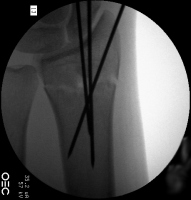

| Percutaneous

fixation. |

| Thermoplastic

stabilization. |